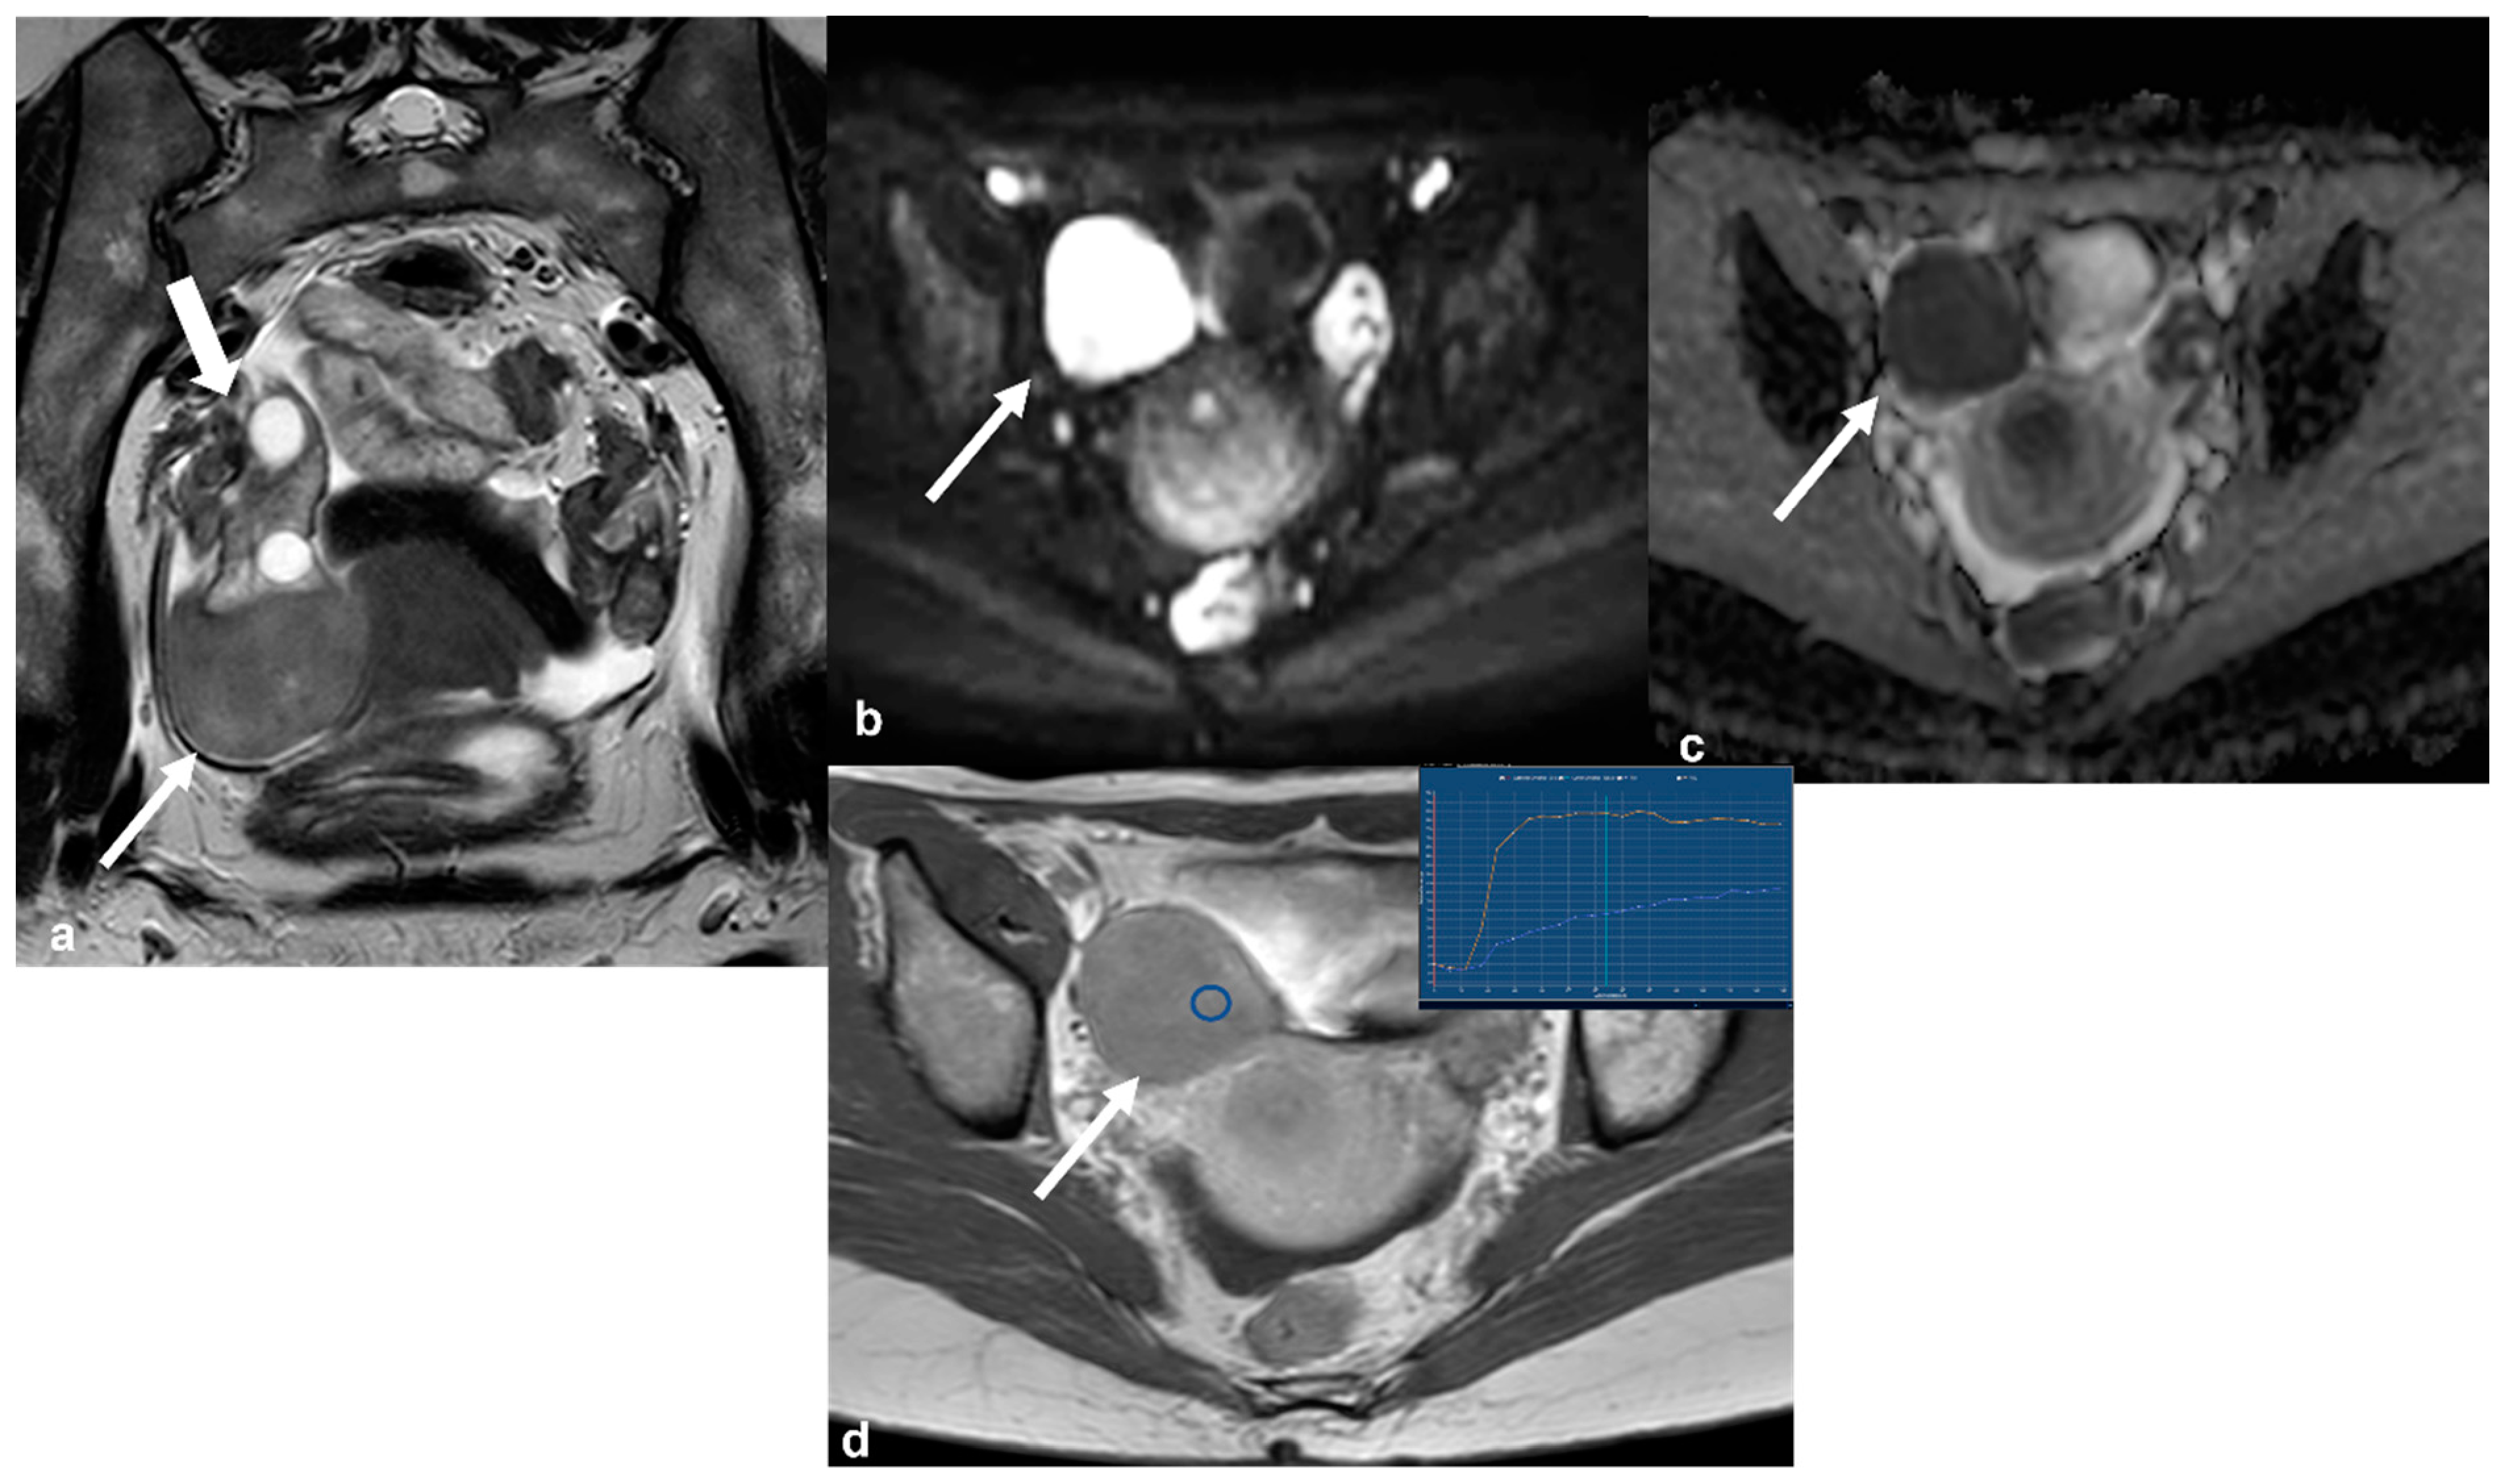

2.3.3. Granulosa Cell Tumor

2.3.4. Lymphoma